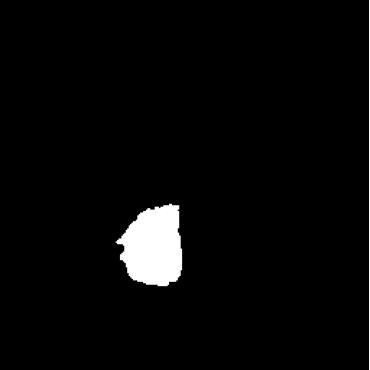

While ACAT revolves around generating counterfactuals, its primary strength lies in accurately identifying pathological regions, which are subsequently employed in a classification pipeline. On the other hand, it falls short in producing credible counterfactual examples, an issue we aim to address in this study. An illustration of this phenomenon is depicted in Figure 2, where we can observe how ACAT is able to generate a saliency map that approximately identifies the pathological region (e, bottom row). However, in the counterfactual example, the lesion remains visible (e, top row). In contrast, our approach not only refines the saliency map but also generates a counterfactual image where the pathology is completely eliminated (f).

We observe that our sampling approach not only generates highly realistic counterfactuals but also enhances the initial saliency maps obtained in the first step using ACAT. This is possible because the selected regions may not undergo complete modification by the diffusion model, allowing for the preservation of healthy anatomical features identified in the initial attribution maps. A visual representation of our approach is presented in Figure 1.